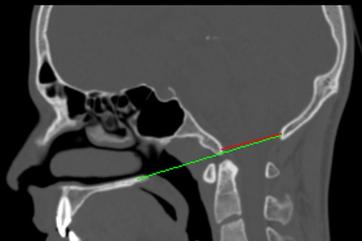

The top of the odontoid is normally at the level of a line drawn from from the hard palate (roof of your mouth) to the base of the occiput.

Pre odontoid      removal (2014)